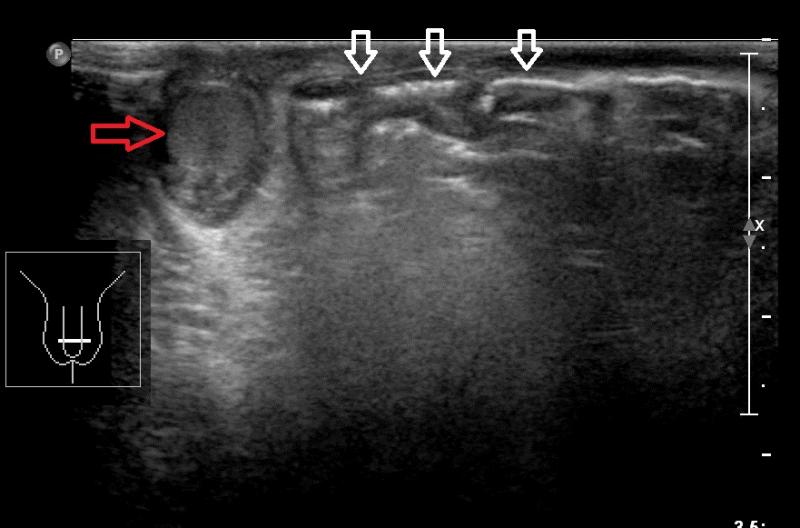

Przypadek 50: 2-miesięczny chłopiec zgłosił się na badanie usg z podejrzeniem przepukliny pachwinowej lewostronnej.

Rozpoznanie: W badaniu usg - uwidoczniono przepuklinę pachwinowę lewostronną - w kanale pachwinowym i w mosznie po stronie lewej widoczne pętle jelitowe (białe strzałki), z zachowaną perystaltyką. Oba jądra widoczne w mosznie, o prawidłowej strukturze i wielkości (czerwona strzałka - jądro prawe, pomarańczowa strzałka - jądro lewe, widoczne poniżej pętli jelitowych).